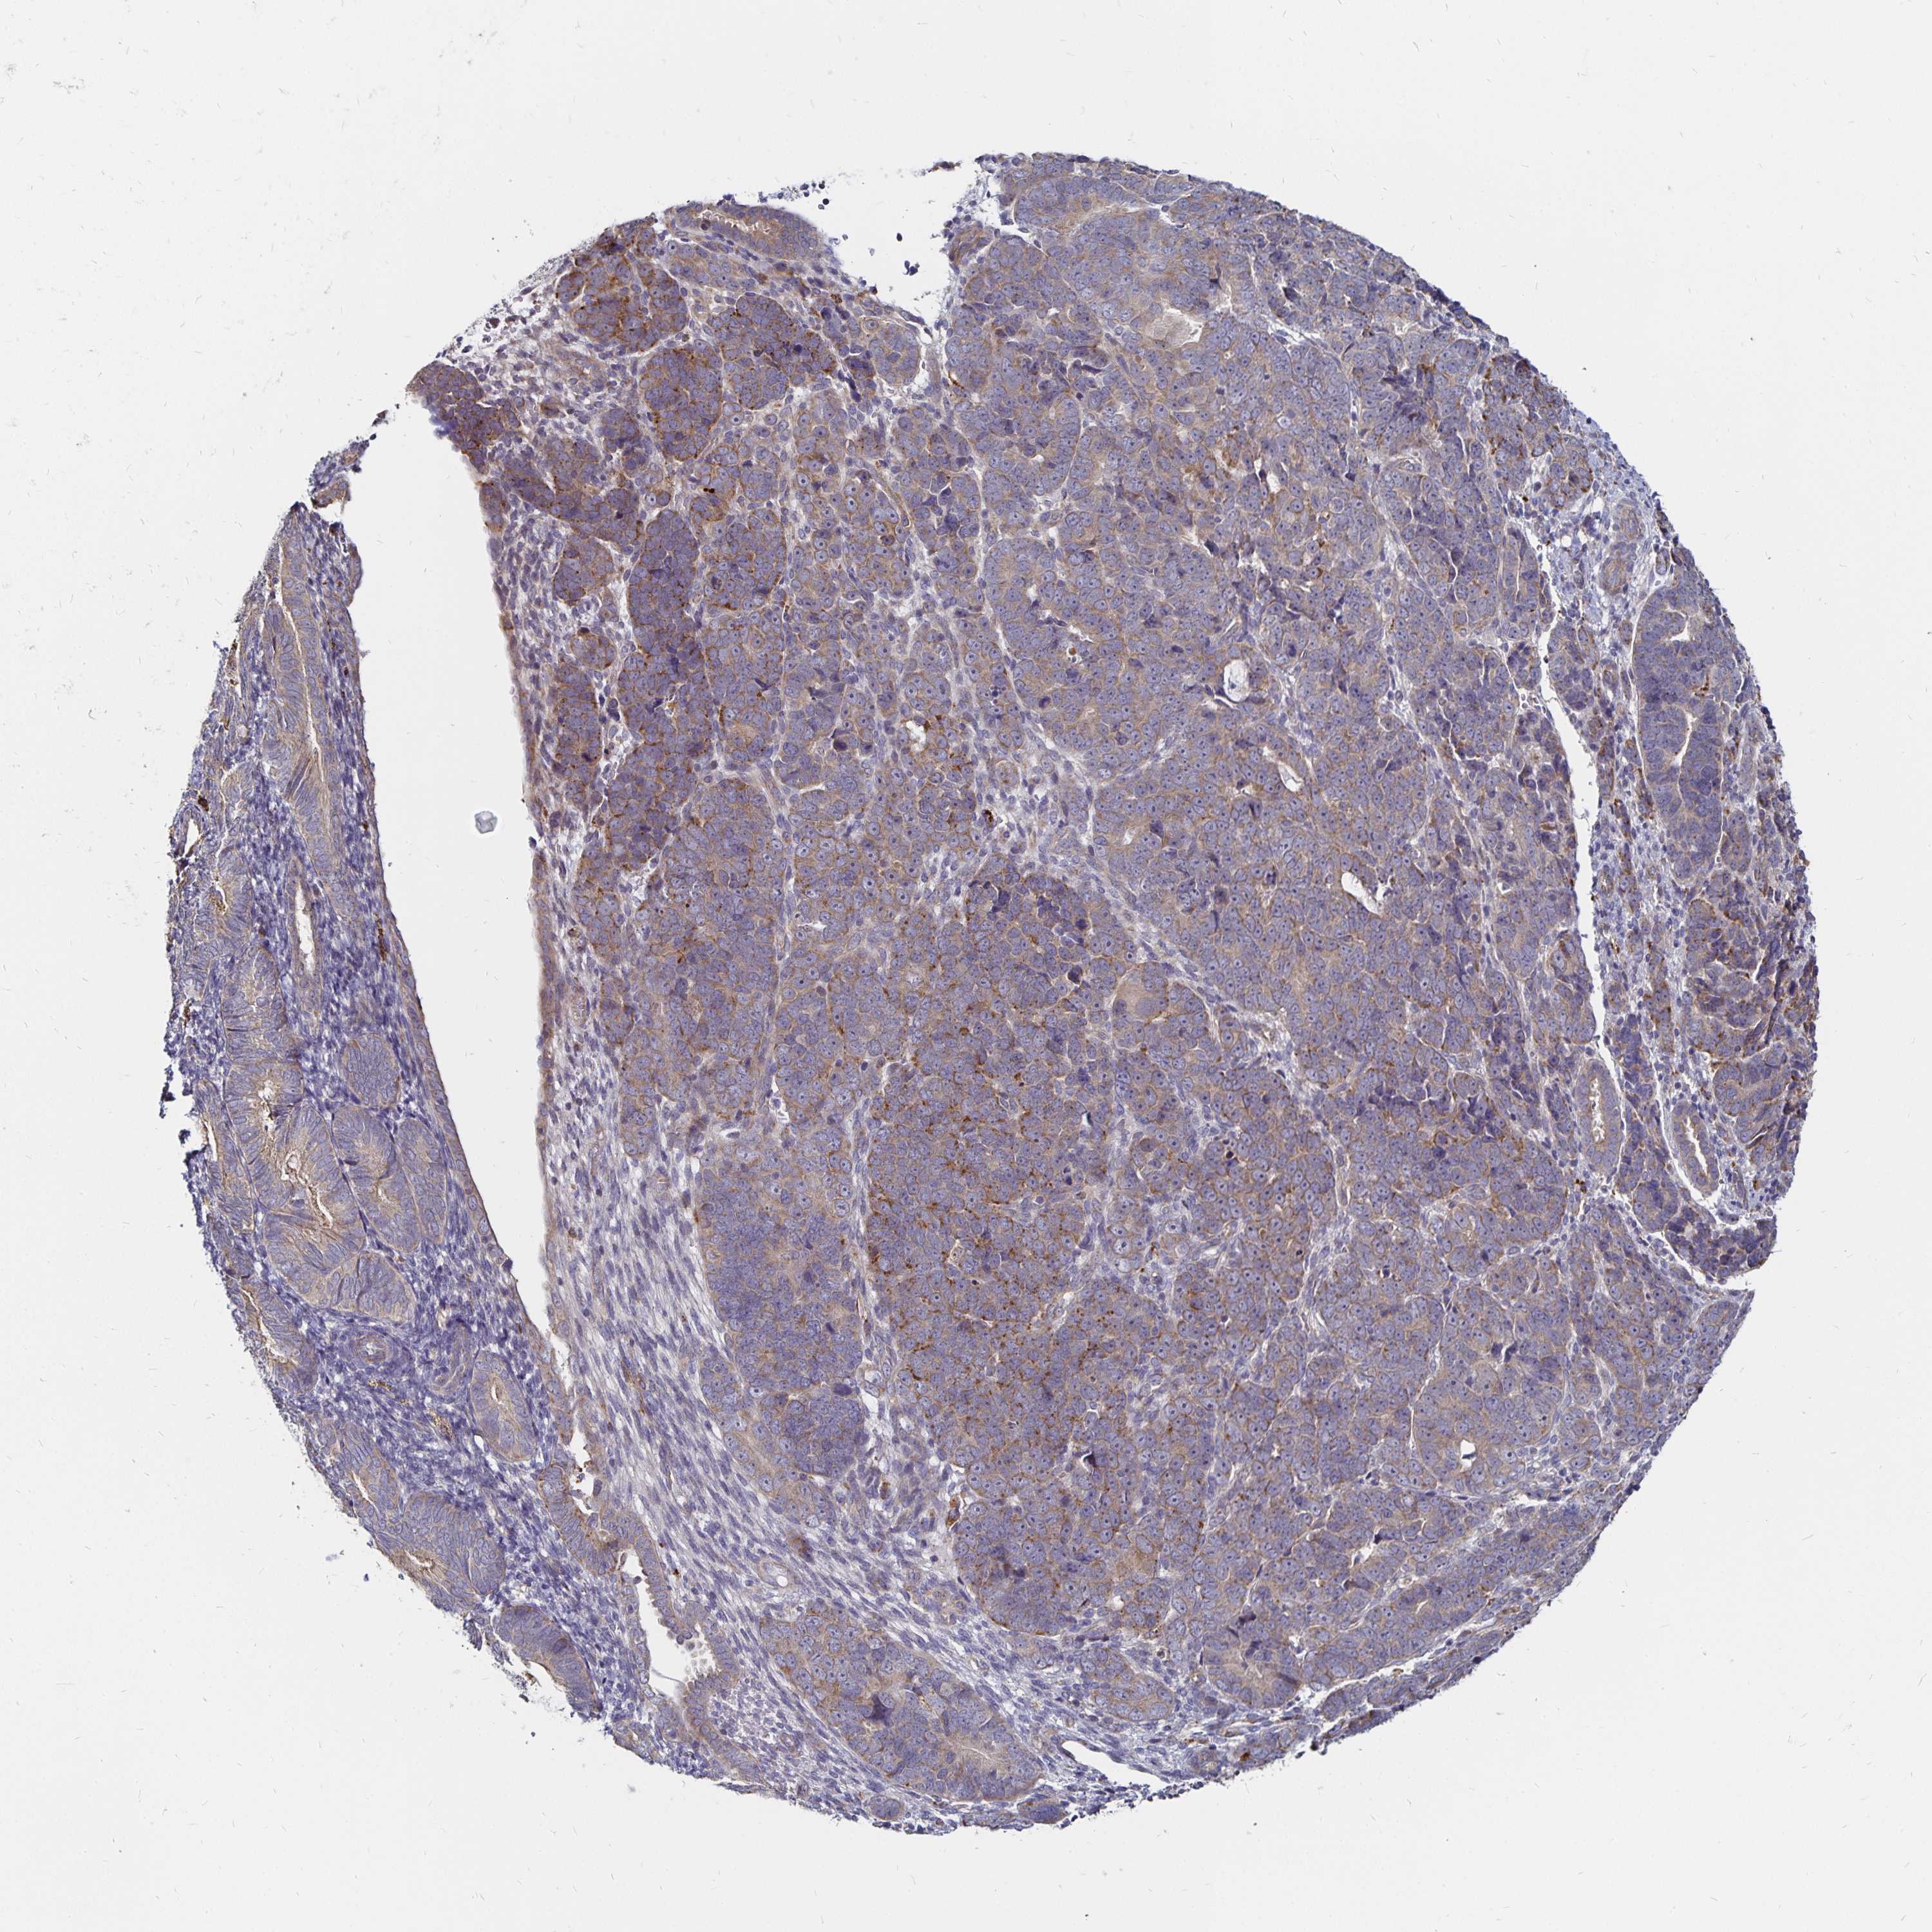

ENDOMETRIAL CANCER - Protein expressioni

A mouse-over function shows sample information and annotation data. Click on an image to view it in a full screen mode. Samples can be filtered based on level of antibody staining by selecting one or several of the following categories: high, medium, low and not detected. The assay and annotation is described here.

Note that samples used for immunohistochemistry by the Human Protein Atlas do not correspond to samples in the TCGA dataset.

Antibody stainingi

Antibody staining in the annotated cell types in the current human tissue is reported as not detected, low, medium, or high, based on conventional immunohistochemistry profiling in selected tissues. This score is based on the combination of the staining intensity and fraction of stained cells.

Each image is clickable and will lead to virtual microscopy that enables deeper exploration of all samples and also displays staining intensity scores, fraction scores and subcellular localization as well as patient and tissue information for each sample.

Antibody HPA059155

Staining

High

Medium

Low

Not detected

Intensity

Strong

Moderate

Weak

Negative

Quantity

>75%

75%-25%

<25%

None

Location

Nuclear

Cytoplasmic/membranous

Cytoplasmic/membranous,nuclear

Adenocarcinoma, NOS

Carcinoma, NOS

Adenocarcinoma, metastatic, NOS